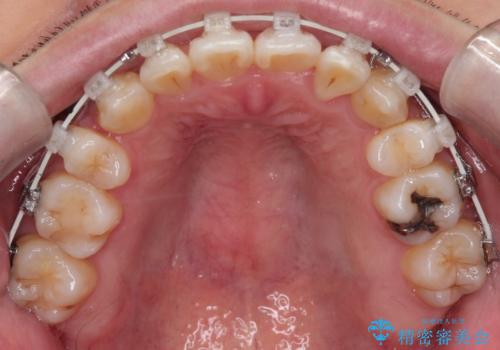

【重度叢生ワイヤー矯正】きれいな歯並びにしたい

- 審美装置

- きれいな歯並びにしたいとの希望を持って来院された患者様です。

上下左右小臼歯を抜歯する治療計画を立て審美装置にて治療を行いました。

骨格的3級傾向もあり、咬合関係を仕上げるのに時間がかかりましたが、患者様には大変満足していただけました。

難しいケースでしたが、矯正用アンカースクリューを用いながら、臼歯関係もきれいに仕上げることができました。